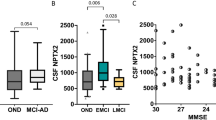

To examine CMRglc measures and corresponding glucose transport (K 1 and k 2) and phosphorylation (k 3) rates in the medial temporal lobe (MTL, comprising the hippocampus and amygdala) and posterior cingulate cortex (PCC) in mild Alzheimer’s disease (AD).

Dynamic FDG PET with arterial blood sampling was performed in seven mild AD patients (age 68 ± 8 years, four females, median MMSE 23) and six normal (NL) elderly (age 69 ± 9 years, three females, median MMSE 30). Absolute CMRglc (μmol/100 g/min) was calculated from MRI-defined regions of interest using multiparametric analysis with individually fitted kinetic rate constants, Gjedde-Patlak plot, and Sokoloff’s autoradiographic method with population-based rate constants. Relative ROI/pons CMRglc (unitless) was also examined.

With all methods, AD patients showed significant CMRglc reductions in the hippocampus and PCC, and a trend towards reduced parietotemporal CMRglc, as compared with NL. Significant k 3 reductions were found in the hippocampus, PCC and amygdala. K 1 reductions were restricted to the hippocampus. Relative CMRglc had the largest effect sizes in separating AD from NL. However, the magnitude of CMRglc reductions was 1.2- to 1.9-fold greater with absolute than with relative measures.

CMRglc reductions are most prominent in the MTL and PCC in mild AD, as detected with both absolute and relative CMRglc measures. Results are discussed in terms of clinical and pharmaceutical applicability.